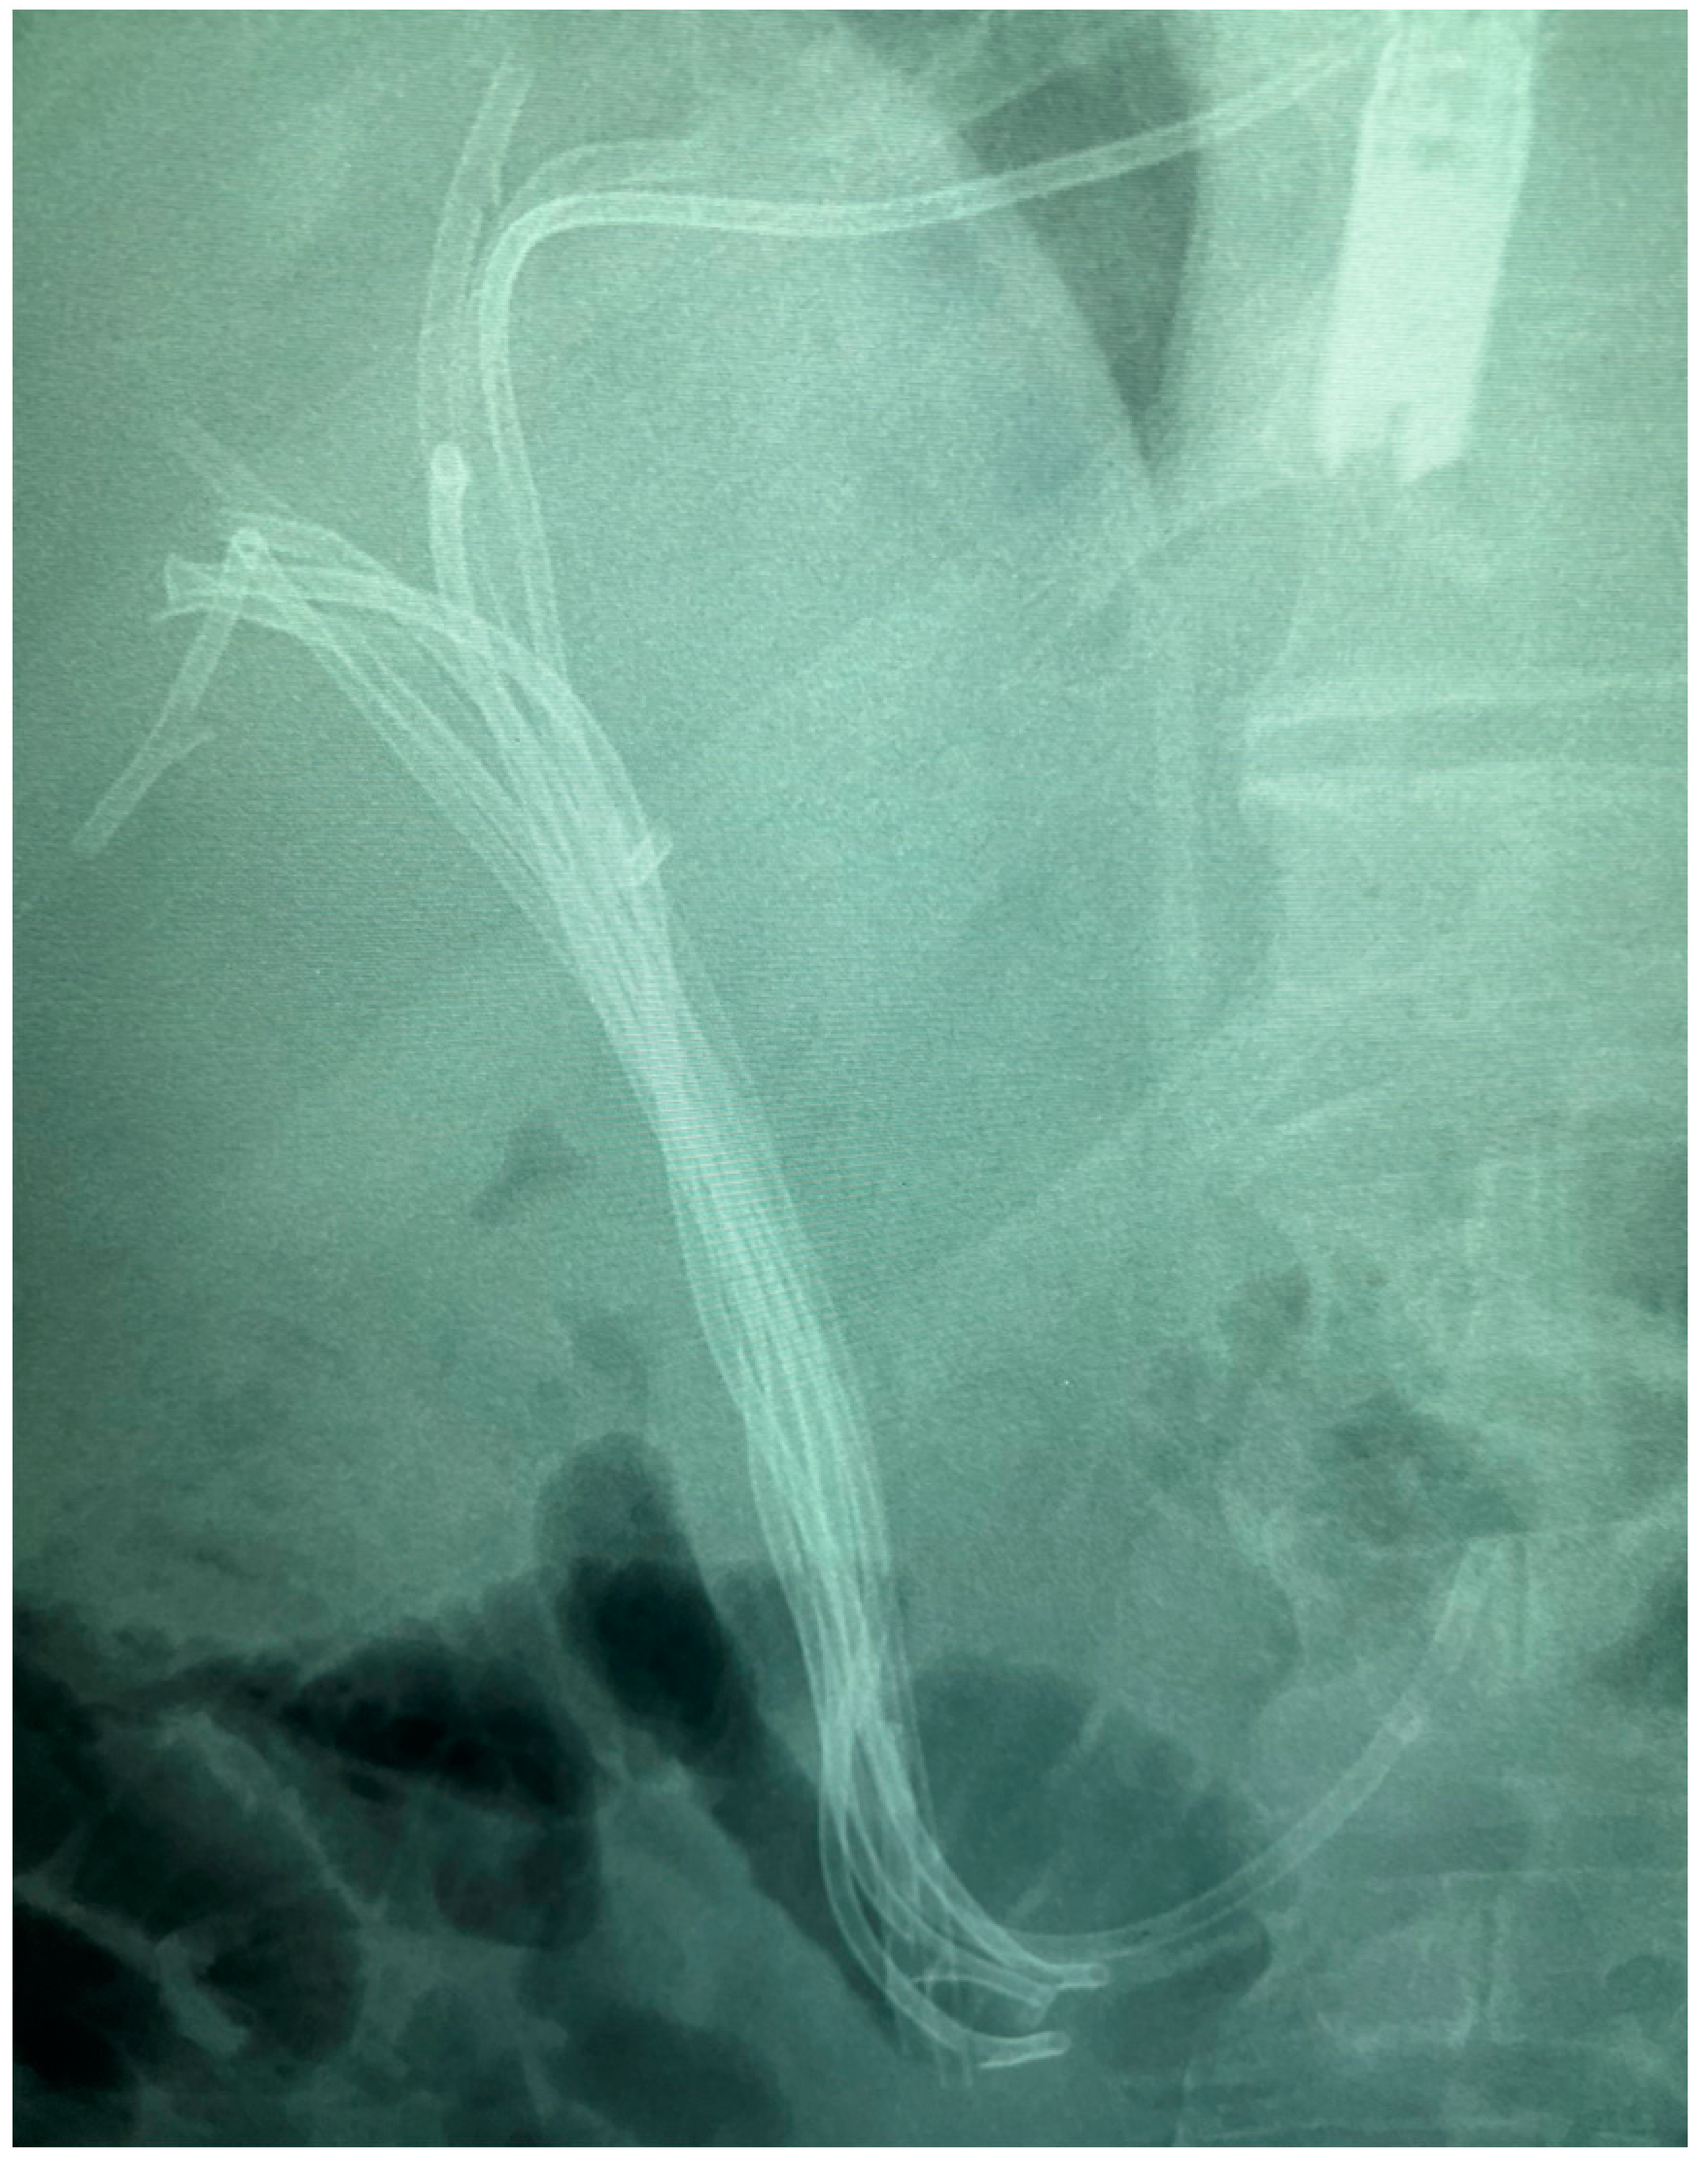

7.1. Endoscopic Guided Biliary Drainage

7.1.1. Endoscopic Biliary Stenting (EBS)

7.1.2. Endoscopic Nasobiliary Drainage (ENDB)